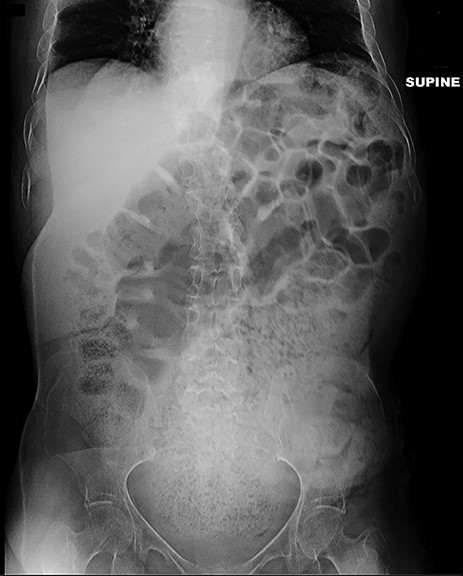

A 64-year-old female who resides in a nursing facility due to significant mental and physical disability presented to the emergency department with a 4-month history of chronic intermittent constipation. She had been treated multiple times for severe constipation and fecal impaction. On presentation, abdominal X-rays exhibited massive stool burden filling the rectum, which was distended cephalad to the diaphragm and anteriorly to the peritoneum occupying much of the abdominal cavity (Fig. 1). The patient was admitted to the hospital and aggressive bowel regimen was initiated with limited improvement. Given a history of multiple failed attempts with pharmacological therapy, surgical intervention was considered. A computed tomography scan of the abdomen showed a massive amount of stool in the rectosigmoid colon with no evidence of an obstructing lesion. The patient had undergone colonoscopy within 2 years of presentation with no evidence of polyps or malignant process. She was chronically malnourished, bedbound, non-communicative putting her at significant risk of morbidity with major intervention. Risks and benefits were discussed with the patient’s family, and it was opted for the least invasive surgical approach. We proceeded with creation of a loop colostomy of the descending colon through a mini left to midline 2.5 cm incision. The patient tolerated the procedure well. Post-operatively, she was treated with antegrade enemas through the distal limb of the colostomy as well as enemas and suppositories per rectum. Subsequent X-rays showed significant decrease in stool burden over the 14-Day period (Fig. 2). She was ultimately discharged to her nursing facility with normal bowel function.

Plain film 2 weeks post-operatively shows significant reduction in stool burden and rectal dilation.